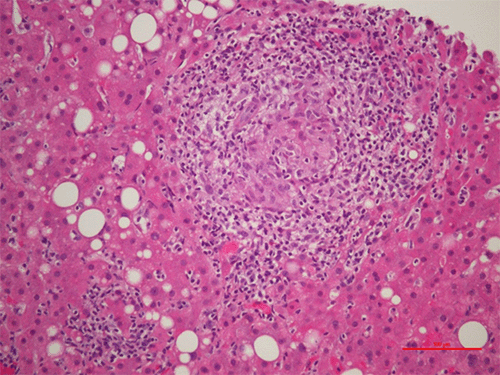

Pathological examination of the resected stomach tissue and a small splenule confirmed non-necrotizing granulomatous inflammation consistent with sarcoidosis (Figure 1).

Figure 3. H&E Staining of Gastric Biopsy Demonstrating Sarcoidosis. Published with Permission

Figure 4. H&E Staining of Liver Biopsy Demonstrating Sarcoidosis. Published with Permission

Gastrointestinal (GI) sarcoidosis is a relatively uncommon manifestation, affecting only 2.5% to 10% of patients with systemic disease, and is often asymptomatic.3,4 Symptomatic GI sarcoidosis is even rarer, with an estimated prevalence of 0.6 to 1%.5 Diagnosis typically relies on EGD with biopsy, but the presenting mucosa can appear normal even when biopsies reveal non-necrotizing granulomas.3 Interestingly, in this case, although gastric sarcoidosis was identified on the initial gastric specimen, there was no evidence of the disease found on preoperative or subsequent postoperative EGD biopsies. The likelihood of missing the diagnosis on endoscopic biopsies, as seen here, remains unclear and warrants further investigation.